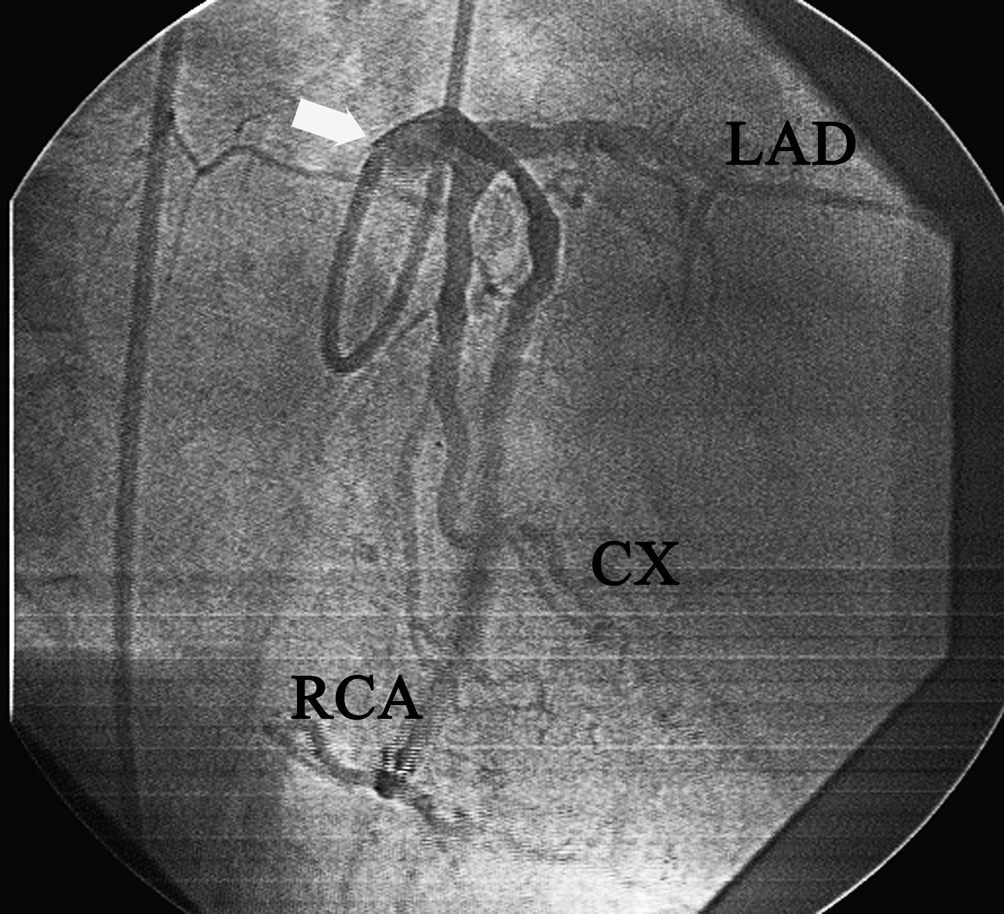

Coronary angiography demonstrated single coronary artery which was a short left main artery and it divided into three branches: left anterior descending (LAD), left circumflex (LCx) and right coronary arteries (RCA). The SCA was originating from the left coronary sinus (CS) via single ostium, classifiable as a Lipton L-I A (Figure 1). Selective angiography did not demonstrate any vessel originating from the right CS. All the coronary branches originated from a single ostium located in the left coronary cusp and had a normal course and distribution. Both the LAD and LCx branches had a normal anterior course and gave rise to the diagonal, septal and obtuse marginal branches, respectively. RCA branch arose from left main trunk and had a normal course and distribution. All of the coronary branches had diffuse atherosclerotic disease (Figure 1). Angiography showed 100% thrombotic occlusion of LAD in the proximal region, 80% stenosis of proximal LCx and 85% stenosis of mid segment of anomalous RCA. Additionally there was a long 90% stenosis due to myocardial bridging in mid portion LAD. Left ventricular systolic function was poor. We thought that the infarct related artery was the thrombotic totally occluded LAD. No other associated cardiac anomaly was detected by cardiac catheterization or echocardiography. Thus it was decided to refer the patient for operation because of three vessel disease and decreased systolic function. The cardiology-cardiovascular surgeons decided on percutaneous interventions of the artery lesions because of high risk of surgery.

Figure 1: Diagnostic coronary angiography showing stenosis of all three coronary arteries of single coronary anomaly before stenting (Right anterior oblique projection) (arrow indicates left main trunk).